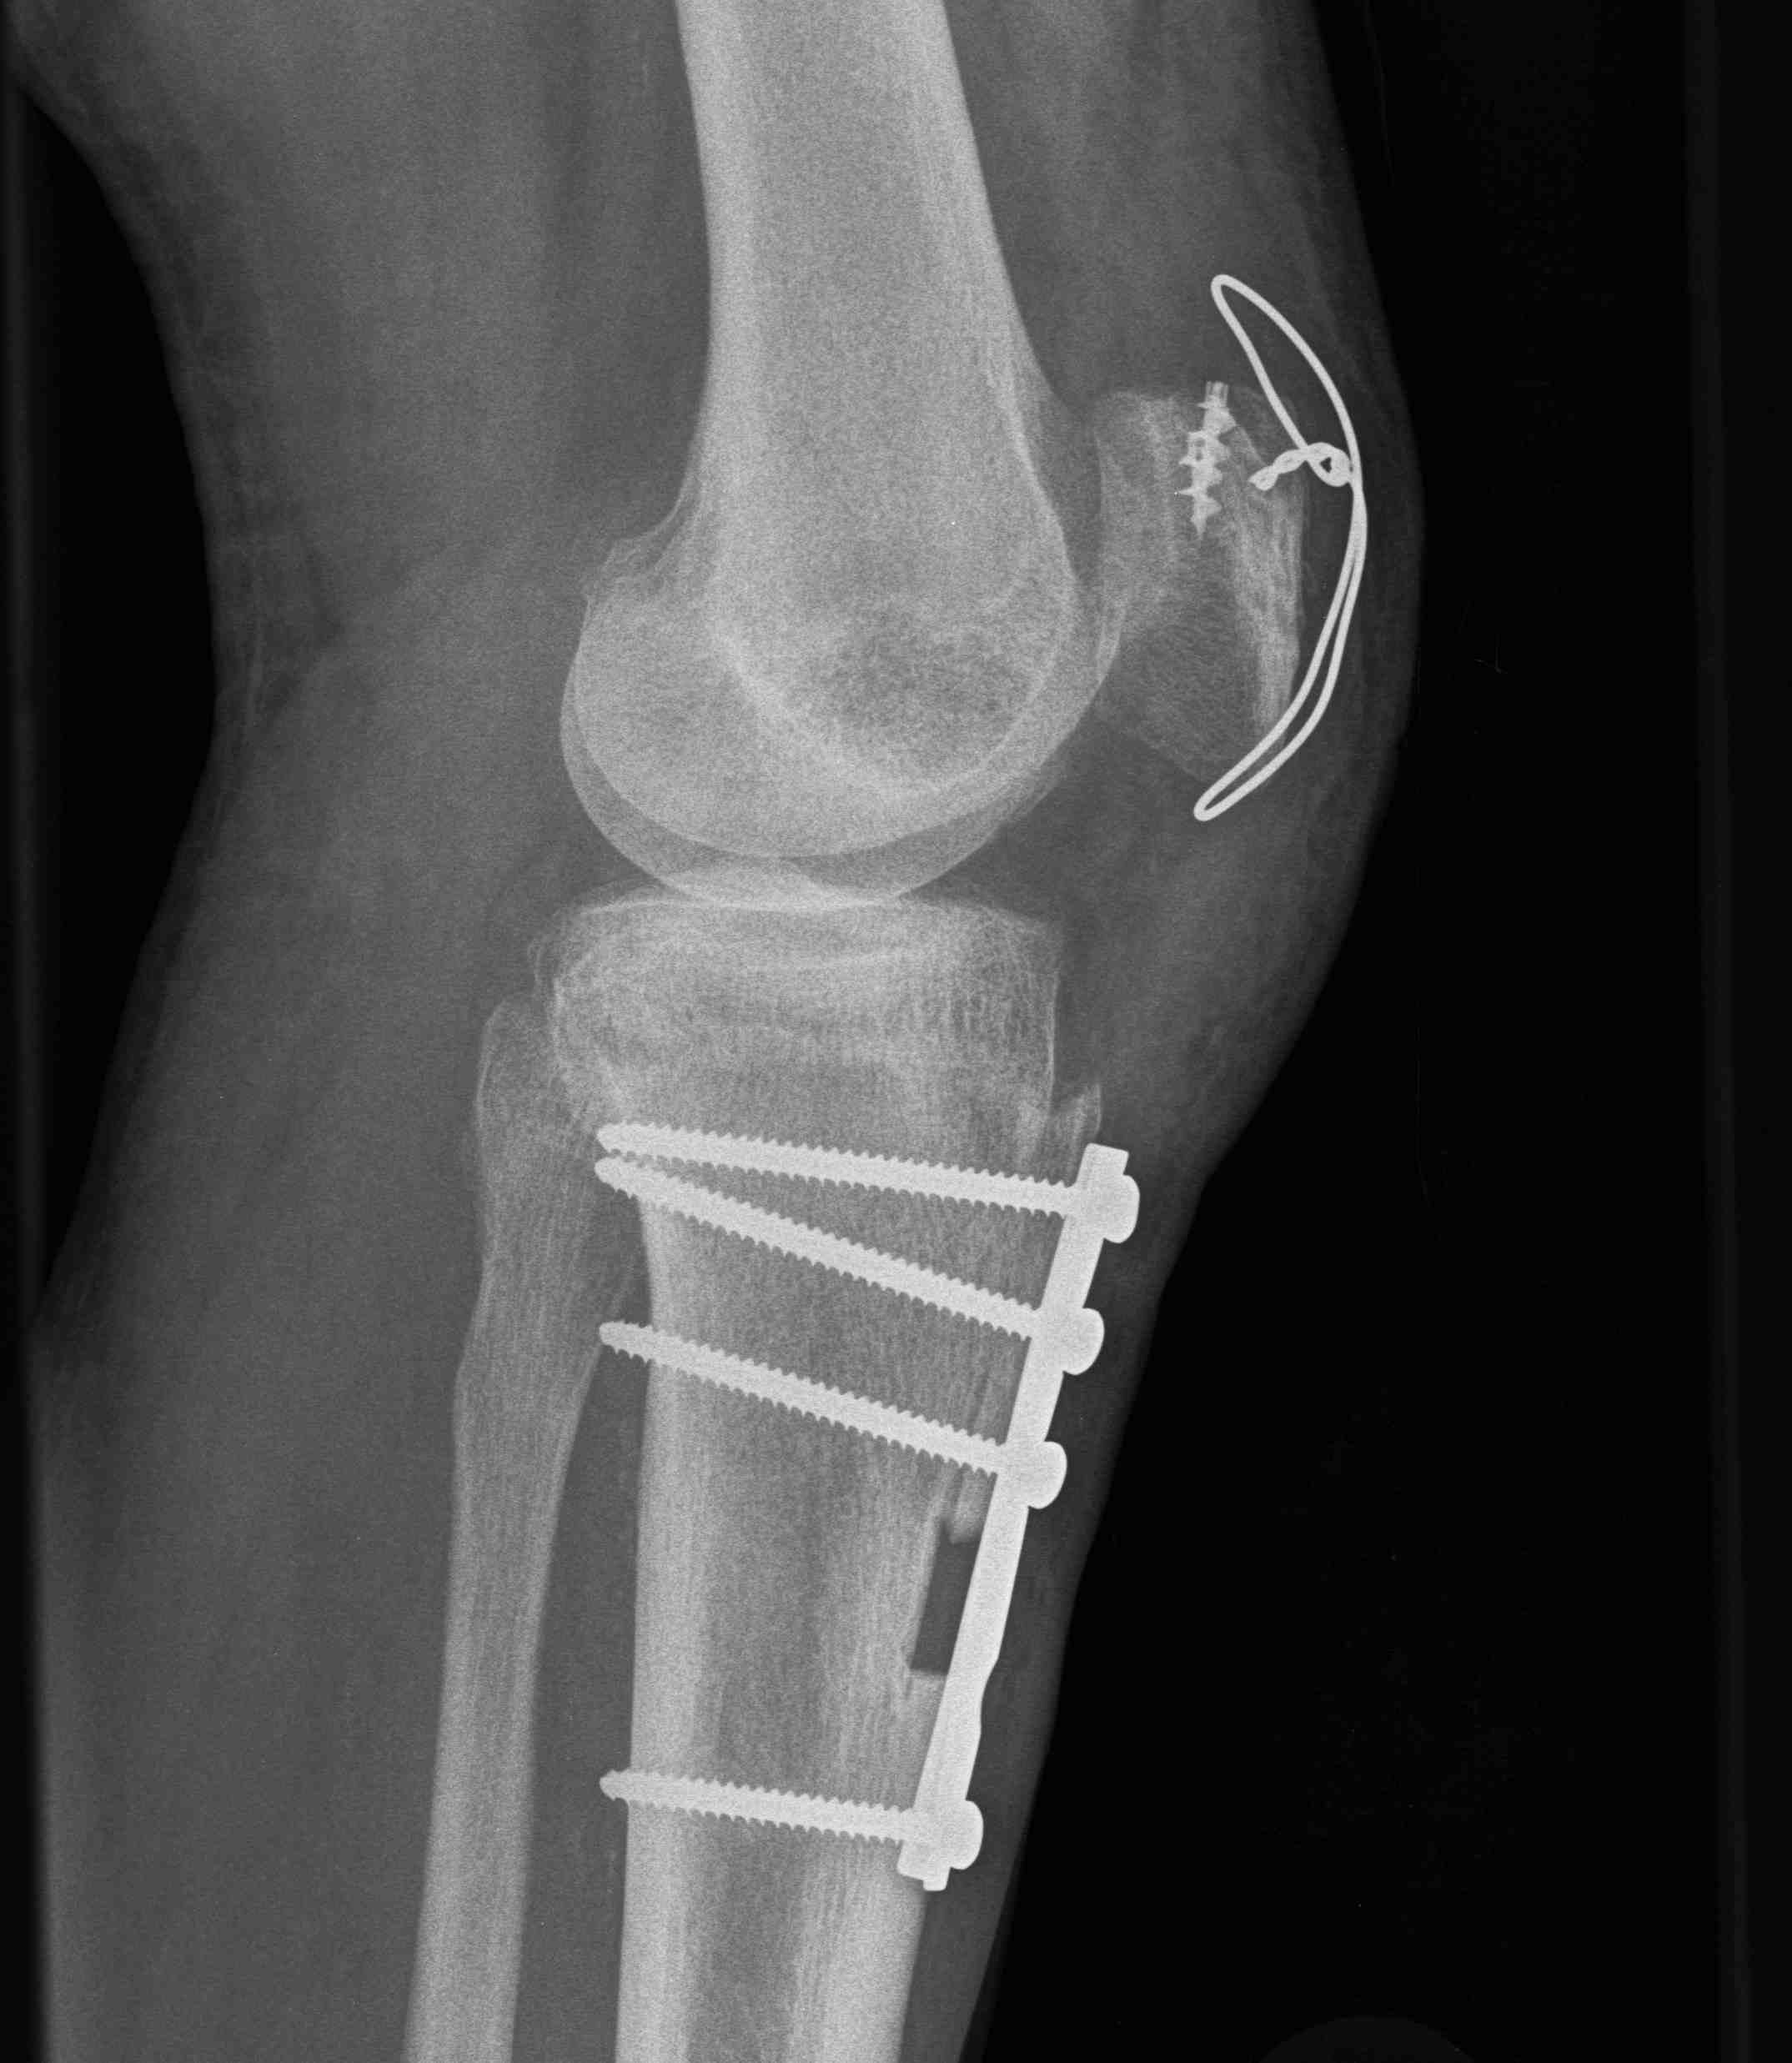

2. Tibial tuberosity osteotomy and proximalization of the patella

Note: Patella Baja with chronic rupture

- patient may develop patella baja

- with chronic injuries / failed injuries

- may need to perform tibial tuberosity osteotomy